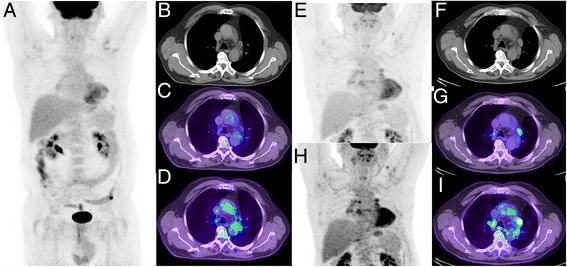

Fig. 2

This patient presented with suspected metastatic nasopharyngeal cancer. Initial workup with endoscopic ultrasound and biopsy of the subcarinal node was non-diagnostic with necrotic tissue. FDG PET/CT demonstrates very intense uptake at all sites with lower uptake in the subcarinal node, only evident when widening the PET window. The findings suggest a different tumour biology at this site  with necrosis. When feasible, we recommend biopsy of the most FDG-avid lesion which likely represents the site of most aggressive disease and least likely to be non-diagnostic. In summary, the PET study windowed narrowly is primed for sensitivity whereas a wider window enables superior characterisation